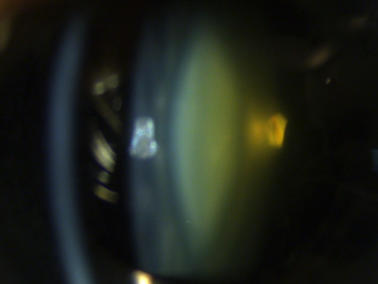

Klare Linse ohne Linsentrübungen

Katarakt („Grauer Star“)